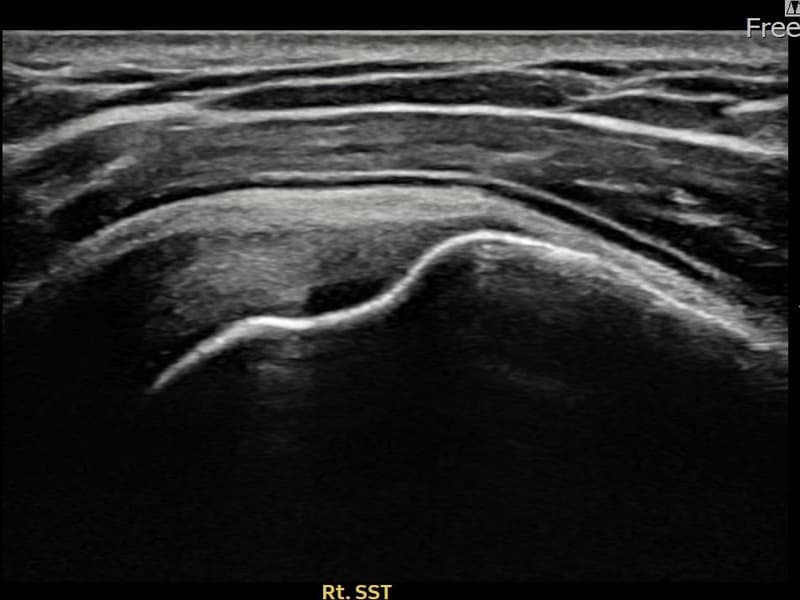

시술 전 초음파 측정 결과 파열 크기는 10mm × 4mm (힘줄 두께의 약 42% 결손)로 확인되었습니다. 시술 전 초음파에서 우측 극상근건 부착부의 에코 단절과 힘줄 결손 소견이 확인되었습니다. 시술 후 초음파에서 부착부 연속성이 회복되고 결손 부위에 재생 조직이 형성된 것이 관찰되었습니다.

50대 초반 남성 환자분으로, 오른쪽 팔을 자주 사용하는 직업 특성상 반복적인 어깨 사용으로 부분파열이 진행되신 분이었습니다. 어깨 외측 통증이 수개월째 지속되고 팔을 들어 올릴 때마다 날카로운 통증이 있어 일상 활동에 큰 불편함이 있으셨습니다. 초음파 검사에서 극상근건 부착부 부분파열이 확인되었으며, 초음파 유도 하 축소봉합술을 시행하였습니다. 시술 후 단계적 재활 운동을 통해 회복을 진행하였고, 시술 13주 후 추적 초음파에서 부착부 힘줄 연속성이 완전히 회복된 것이 확인되어 정상 업무에 복귀하셨습니다.